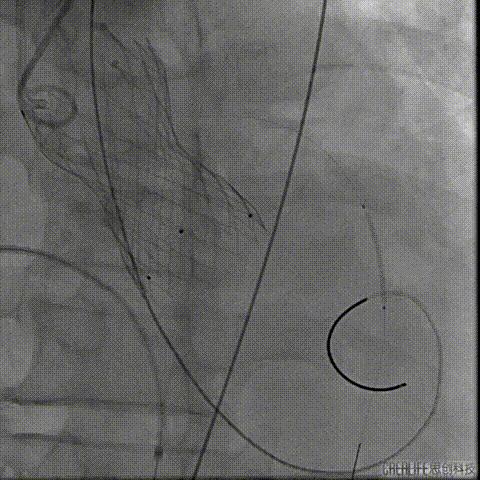

预扩主动脉瓣

NUMED 25mm*40球囊

180/分起搏下预扩主动脉瓣

左冠血流受到影响

予ECOM支持

扩瓣结束后,患者出现心跳骤停

予胸外按压,并予ECOM支持后

患者恢复自主心率

经桡冠脉保护